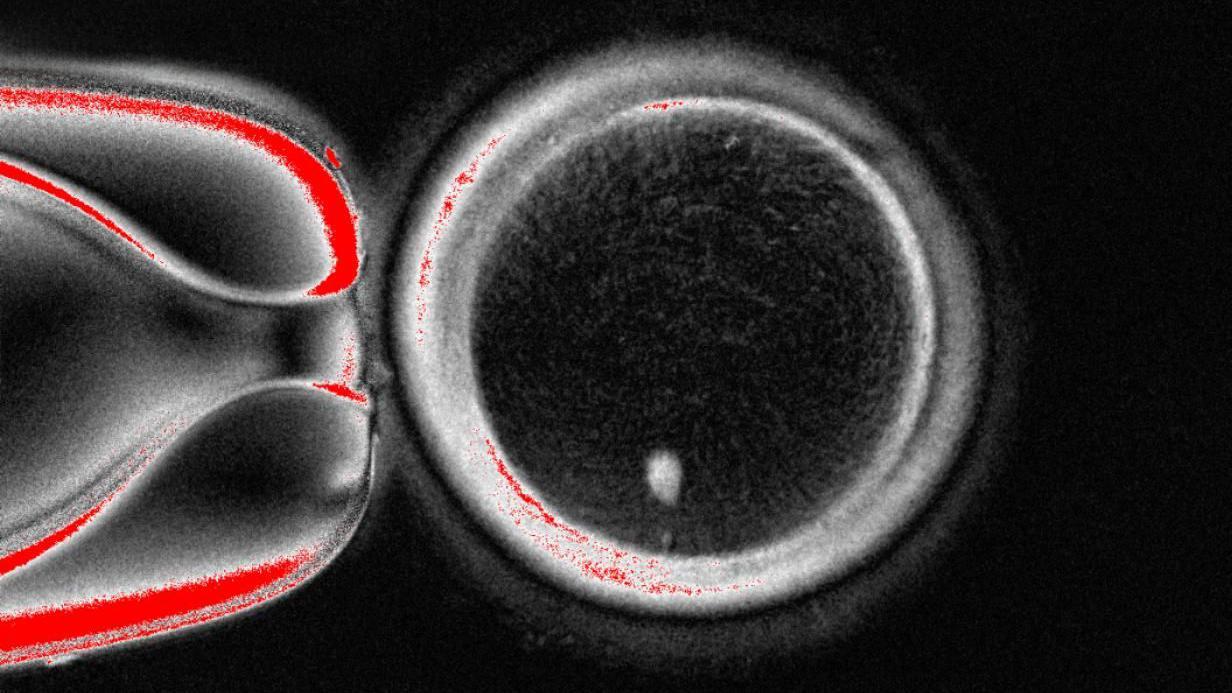

The research group from Oregon Health and Science University’s method involves removing the nucleus, which contains a copy of the complete genetic information required to form the body, from a skin cell.

It is subsequently inserted into a donor egg that has had its genetic information removed.

So far, the method resembles the one employed to produce Dolly the Sheep—the first cloned mammal in the world—which came into existence in 1996.

Nevertheless, this egg is not prepared to be fertilized by sperm since it already has a complete set of chromosomes.

You receive 23 of these DNA groups from each parent, making a total of 46, which the egg already contains.

Therefore, the following step involves convincing the egg to eliminate half of its chromosomes through a process that the scientists have called “mitomeiosis” (a term combining mitosis and meiosis, the two methods by which cells divide).

The study, appeared in the journal Nature Communications, demonstrated that 82 functional eggs were produced. These were fertilized with sperm, and some advanced to the early stages of embryo development. None developed beyond the six-day stage.